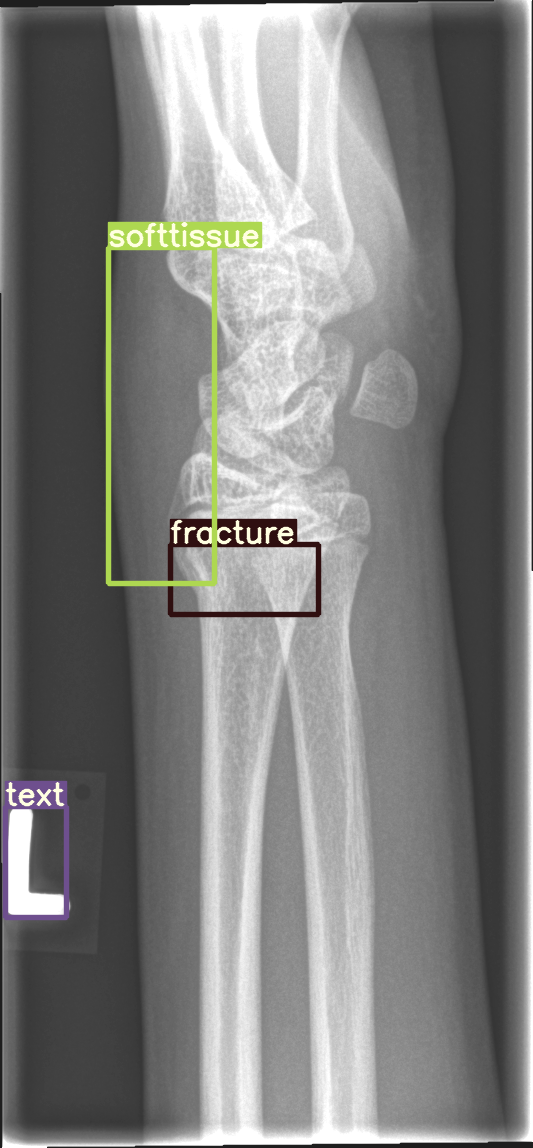

Refer to caption

Figure 4: Bounding box-annotated X-ray images of pediatric wrist trauma from the GRAZPEDWRI-DX dataset [8].

For our experiments, we selected the GRAZPEDWRI-DX images with bounding box annotations in YOLO format, which contains nine classes. Following the data division and augmentation approach outlined by [10], the dataset was randomly divided into 70%percent7070\%70 % training (14,2341423414,23414 , 234 images), 20%percent2020\%20 % validation (4,06540654,0654 , 065 images), and 10%percent1010\%10 % testing (2,02820282,0282 , 028 images) sets. To further augment the training data, the number of images in the training set was doubled by adjusting the contrast and luminance of the images. The label distribution and bounding box statistics are shown in Figure 3. Examples of two training images with bounding box annotations from the GRAZPEDWRI-DX dataset are shown in Figure 4.